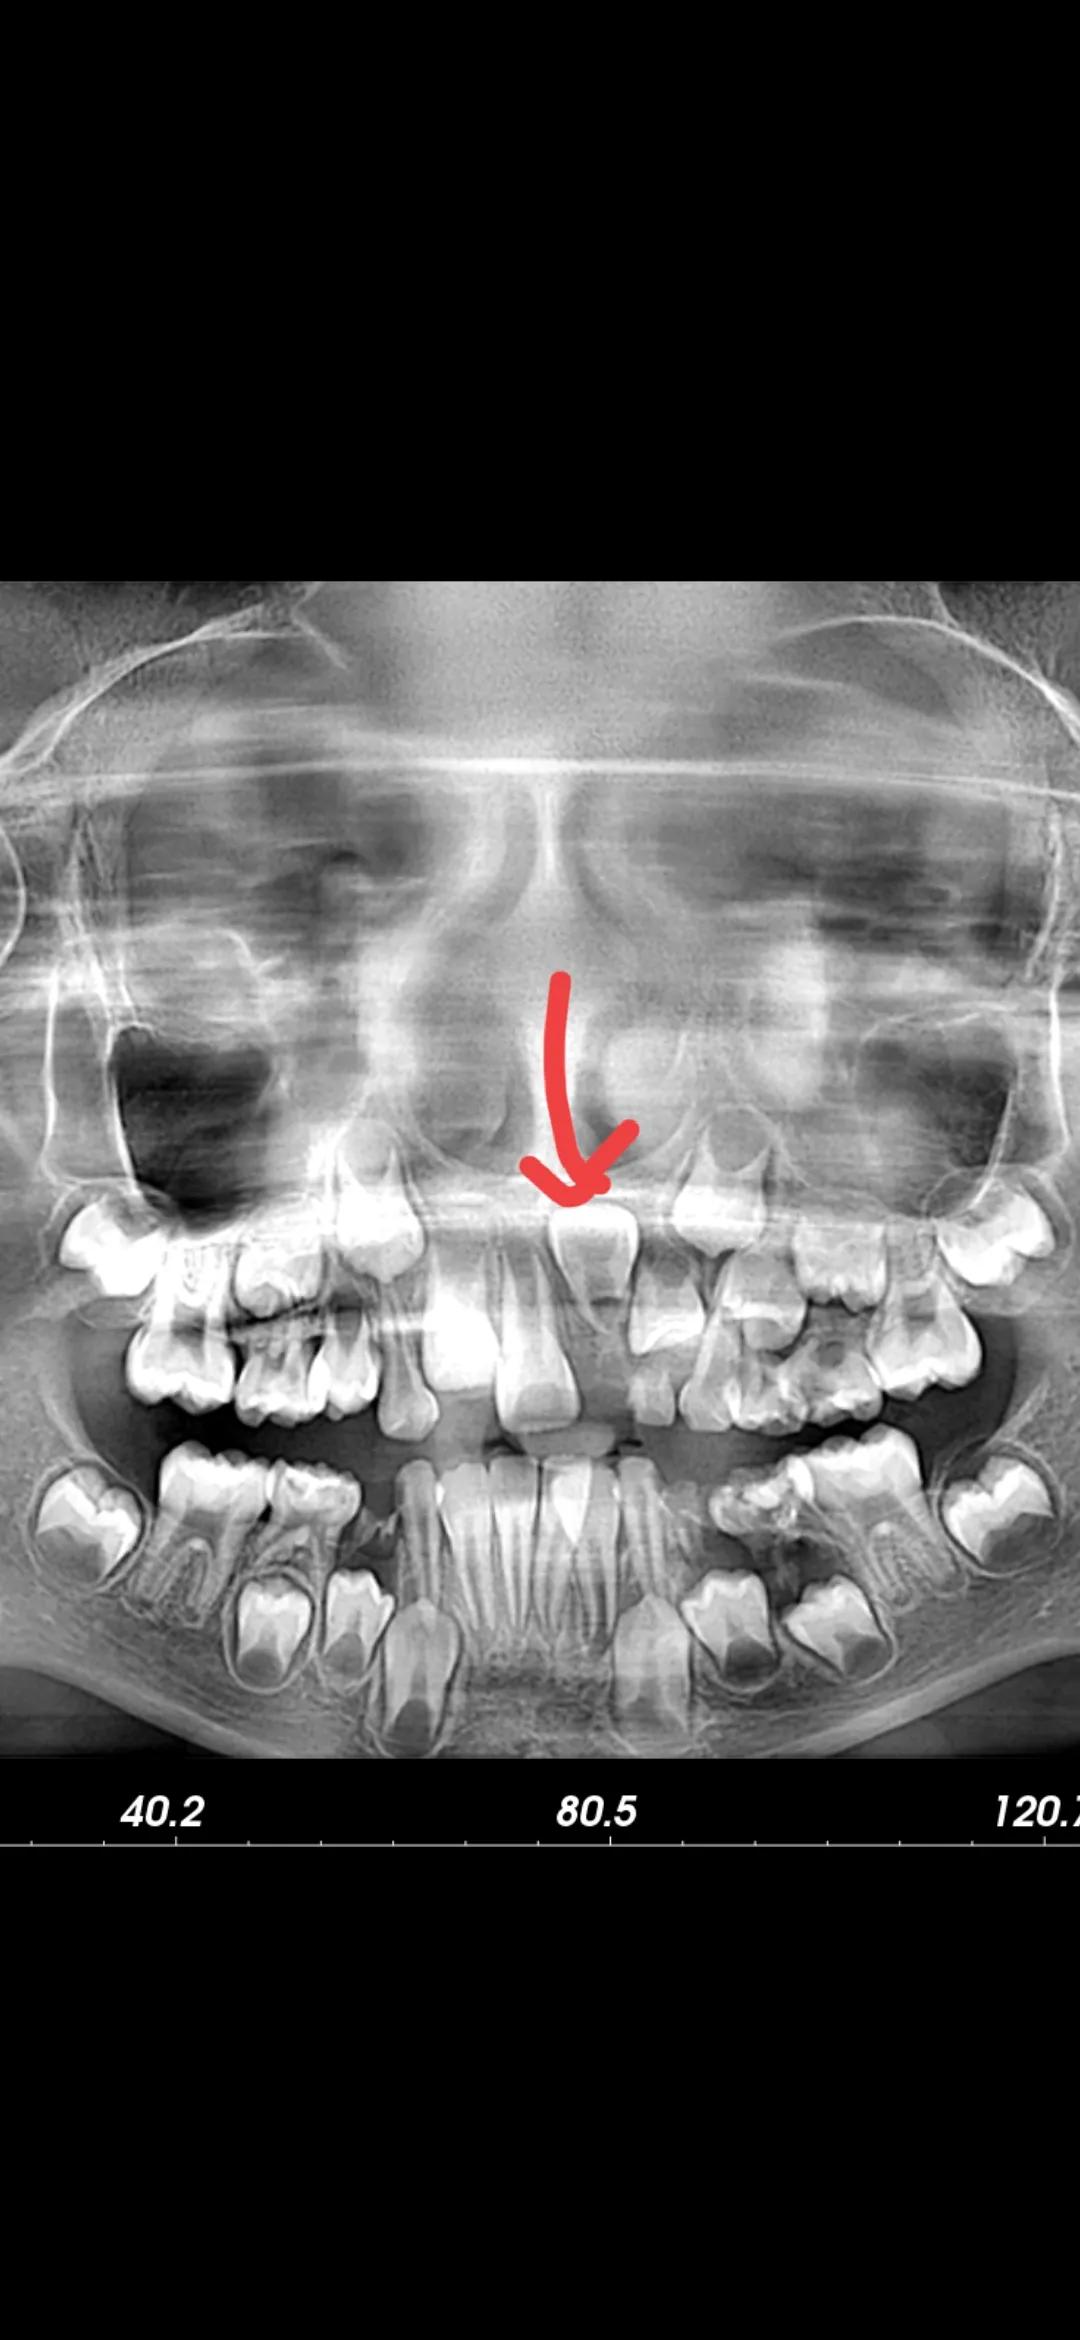

大家可以看到这是我们最近接到的一个病历情况。孩子8岁了乳牙已经掉了,但是门牙一直没有长。家长等不下去了带孩子来检查拍了片子才发现原来门牙倒着长的,类似这种情况有很多是可以提前求助医生进行早期干预的。